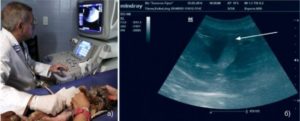

Диагностика сладж синдрома основывается на данных УЗИ или гастродуоденального зондирования желчного пузыря.

примеры билиарного сладжа

- УЗИ желчного пузыря позволяет определить анатомические параметры и оценить состояние органа, выявить холестаз, холестероз, фиброз, сгустки, конгломераты, хлопьевидный осадок в желчи, определить ее количество. До сих пор ученые-медики не определили, является ли сладж синдром самостоятельным заболеванием или только УЗИ-симптомом. Это связано с отсутствием прогноза патологии, эффективных лечебных схем и тактики ведения пациентов.

Назначение оптимального лечения требует провести обследование. Гастроэнтеролог должен обнаружить аномалию на ранней стадии. Первым назначаемым обследованием обычно бывает УЗИ, где определяется тип сладжа (осадка). Состав и классификация осадка условно разделяет взвеси на три типа:

Основной метод обнаружения осадка — УЗИ. Главными показаниями к обследованию пациента служат болезненные ощущения в животе, а также анализы печеночных проб и крови.